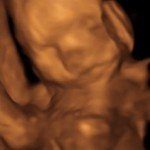

4D/5D/HD Ultrasound Gallery

Gallery